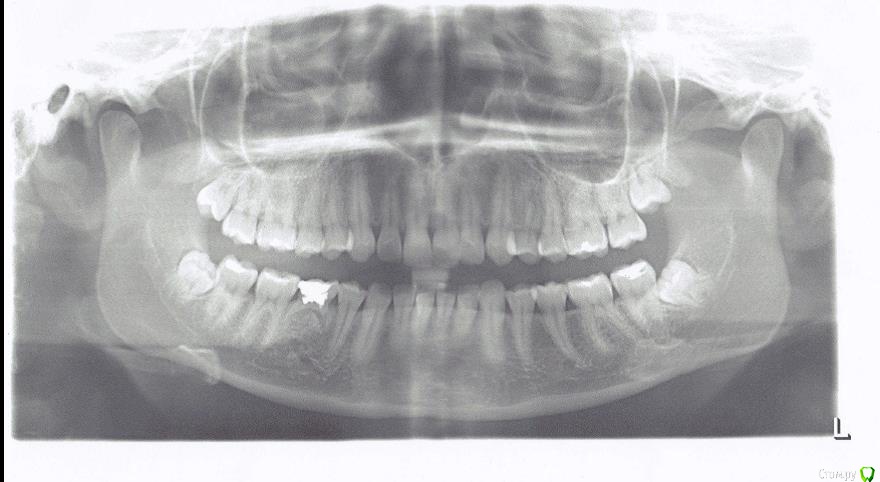

Kristina20 Опубликовано 28 мая, 2015 Поделиться Опубликовано 28 мая, 2015 (изменено) Добрый день. Ж, 20 лет.Требуется ли удаление нижних 8? Правая 8 периодически напоминает о себе,2-3 дня болит, потом замолкает на месяц. Слева болей нет. В переднем отделе небольшая скученность уже есть, не будут ли мне 8ки сдвигать зубы еще сильнее? Изменено 28 мая, 2015 пользователем Kristina20 Ссылка на комментарий

AlexanderGudkov Опубликовано 28 мая, 2015 Поделиться Опубликовано 28 мая, 2015 (изменено) Я бы рекомендовал удалять. Усугубление скученности не исключено. Во-вторых есть риск что седьмые зубы могут испортиться. В-третьих может обостриться перекоронит и доставить вагон проблем У вас слишком много зубов на нижней челюсти (молочный зуб, кстати не выпал) это способствует скученности Изменено 28 мая, 2015 пользователем AlexanderGudkov 1 Ссылка на комментарий

faity Опубликовано 29 мая, 2015 Поделиться Опубликовано 29 мая, 2015 1.8, 2.8, 3.8, 8.5, 4.8 удалять, ставить брекеты, имплантировать 4.5, протезировать Ссылка на комментарий

AlexanderGudkov Опубликовано 29 мая, 2015 Поделиться Опубликовано 29 мая, 2015 А 1.8 и 2.8 почему на удаление?Эти зубы никогда не будут функционировать. Они лишь будут создавать депо зубного налета, инфекции Ссылка на комментарий